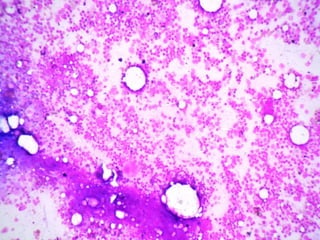

A 55-year-old female presented with pancytopenia and spleenomegaly. Bone marrow aspiration was dry but imprint smears and biopsy showed relevant findings. A 30-year-old male presented with upper GI obstruction and was found to have an ulcerative duodenal lesion. He underwent Whipple's operation and imaging found enlarged pancreaticoduodenal and paraaortic nodes with mild hepatosplenomegaly. Micrographs of lymph nodes were submitted. A 65-year-old male presented with abdominal discomfort and CT scan showed multiple enlarged retroperitoneal and mesenteric nodes without hepatosplenomegaly; a biopsy of a retroperitoneal lymph node was submitted.